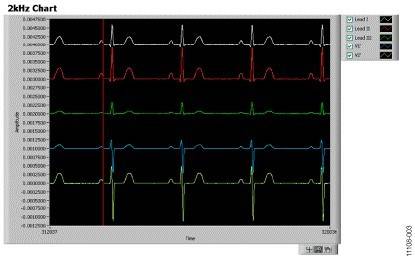

For detailed instructions on how to use the ADAS1000 evaluation board, refer to the ADAS1000SDZ User Guide. Figure 3 shows a typical screen shot using the evaluation board software with the evaluation board connected to a patient simulator.

Figure 3. Screen shot of the ADAS1000 connected to the patient simulator, heart rate = 70 BPM.